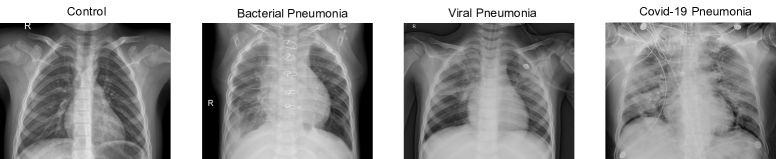

We have used the dataset available in Kaggle (2020b) for controls and patients who suffered from a bacterial or a no-COVID19 pneumonia. According to the information described in Kermany et al. (2018), the CXR images were selected from retrospective cohorts of pediatric patients of one to five years old from Guangzhou Women and Children’s Medical Center, Guangzhou. All CXR images were obtained as part of patient’s routines clinical care. Institutional Review Board (IRB)/Ethics Committee approvals were obtained. The work was conducted in a manner compliant with the United States Health Insurance Portability and Accountability Act (HIPAA) and was adherent to the tenets of the Declaration of Helsinki. Kermany et al. (2018) collected and labeled a total of 6374 CXR images from children, including 4273 characterized as depicting pneumonia and 1583 normal. From those patients diagnosed with pneumonia, 2786 were labeled as bacterial pneumonia, whereas 1487 were labeled as viral pneumonia. The dataset containing COVID-19 patients is available in Kaggle (2020a) and includes 576 CXR images from adults. Figure 1 shows the CXR image from a control (CTL), and a patient suffering from a bacterial (BAC), a viral (VIR) and a COVID19 (CVD19) pneumonia.

Fig. 1: From left to right, CXR image of a control, bacterial pneumonia, viral pneumonia and COVID-19 pneumonia. Note some clear artifacts in COVID-19 image.